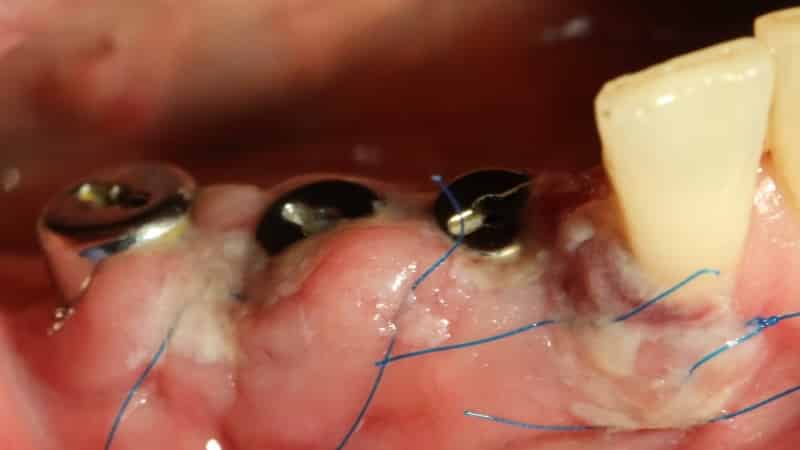

Установка зубного импланта. Этот процесс может занять около часа. Во время установки специалист делает разрез в десне, вживляет штифты и корни импланта, а затем зашивает разрез. Процедура проводится под общим или местным наркозом в зависимости от пожеланий и показаний пациента. После этого начинается длительный процесс заживления, который может занять около 3-4 месяцев, а иногда и до полугода.

Прикрепление абатмента – импланта. Во время этой процедуры специалист вкручивает формирователь десны, который выступает в ротовую полость. Через некоторое время, обычно несколько дней, формирователь удаляется, и на его место прикрепляется зубной протез.